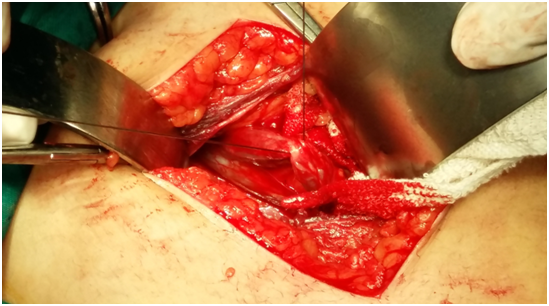

A 31 years old married female Gravida 4 para 4 having four children, presented to our clinic with a similar history of six years of chronic lower abdominal pain, exacerbated with menstruation the patient complain of vaginal discharge and a history of extensive lower extremity varicose veins in left leg treated two years back by stripping of long saphenous vein and multiple avulsion (Figure 2).

Figure 2 Case 2 Multi slices Ct Angiography showing dilated pelvic veins extending to dilated Lt Ovarian Vein.

Specific investigation for both patients consisted of Colored Ecko Doppler followed by performance of Multislice Computerized Angiography, proved the presence of pelvic varicosities with dilated Lt Ovarian vein.